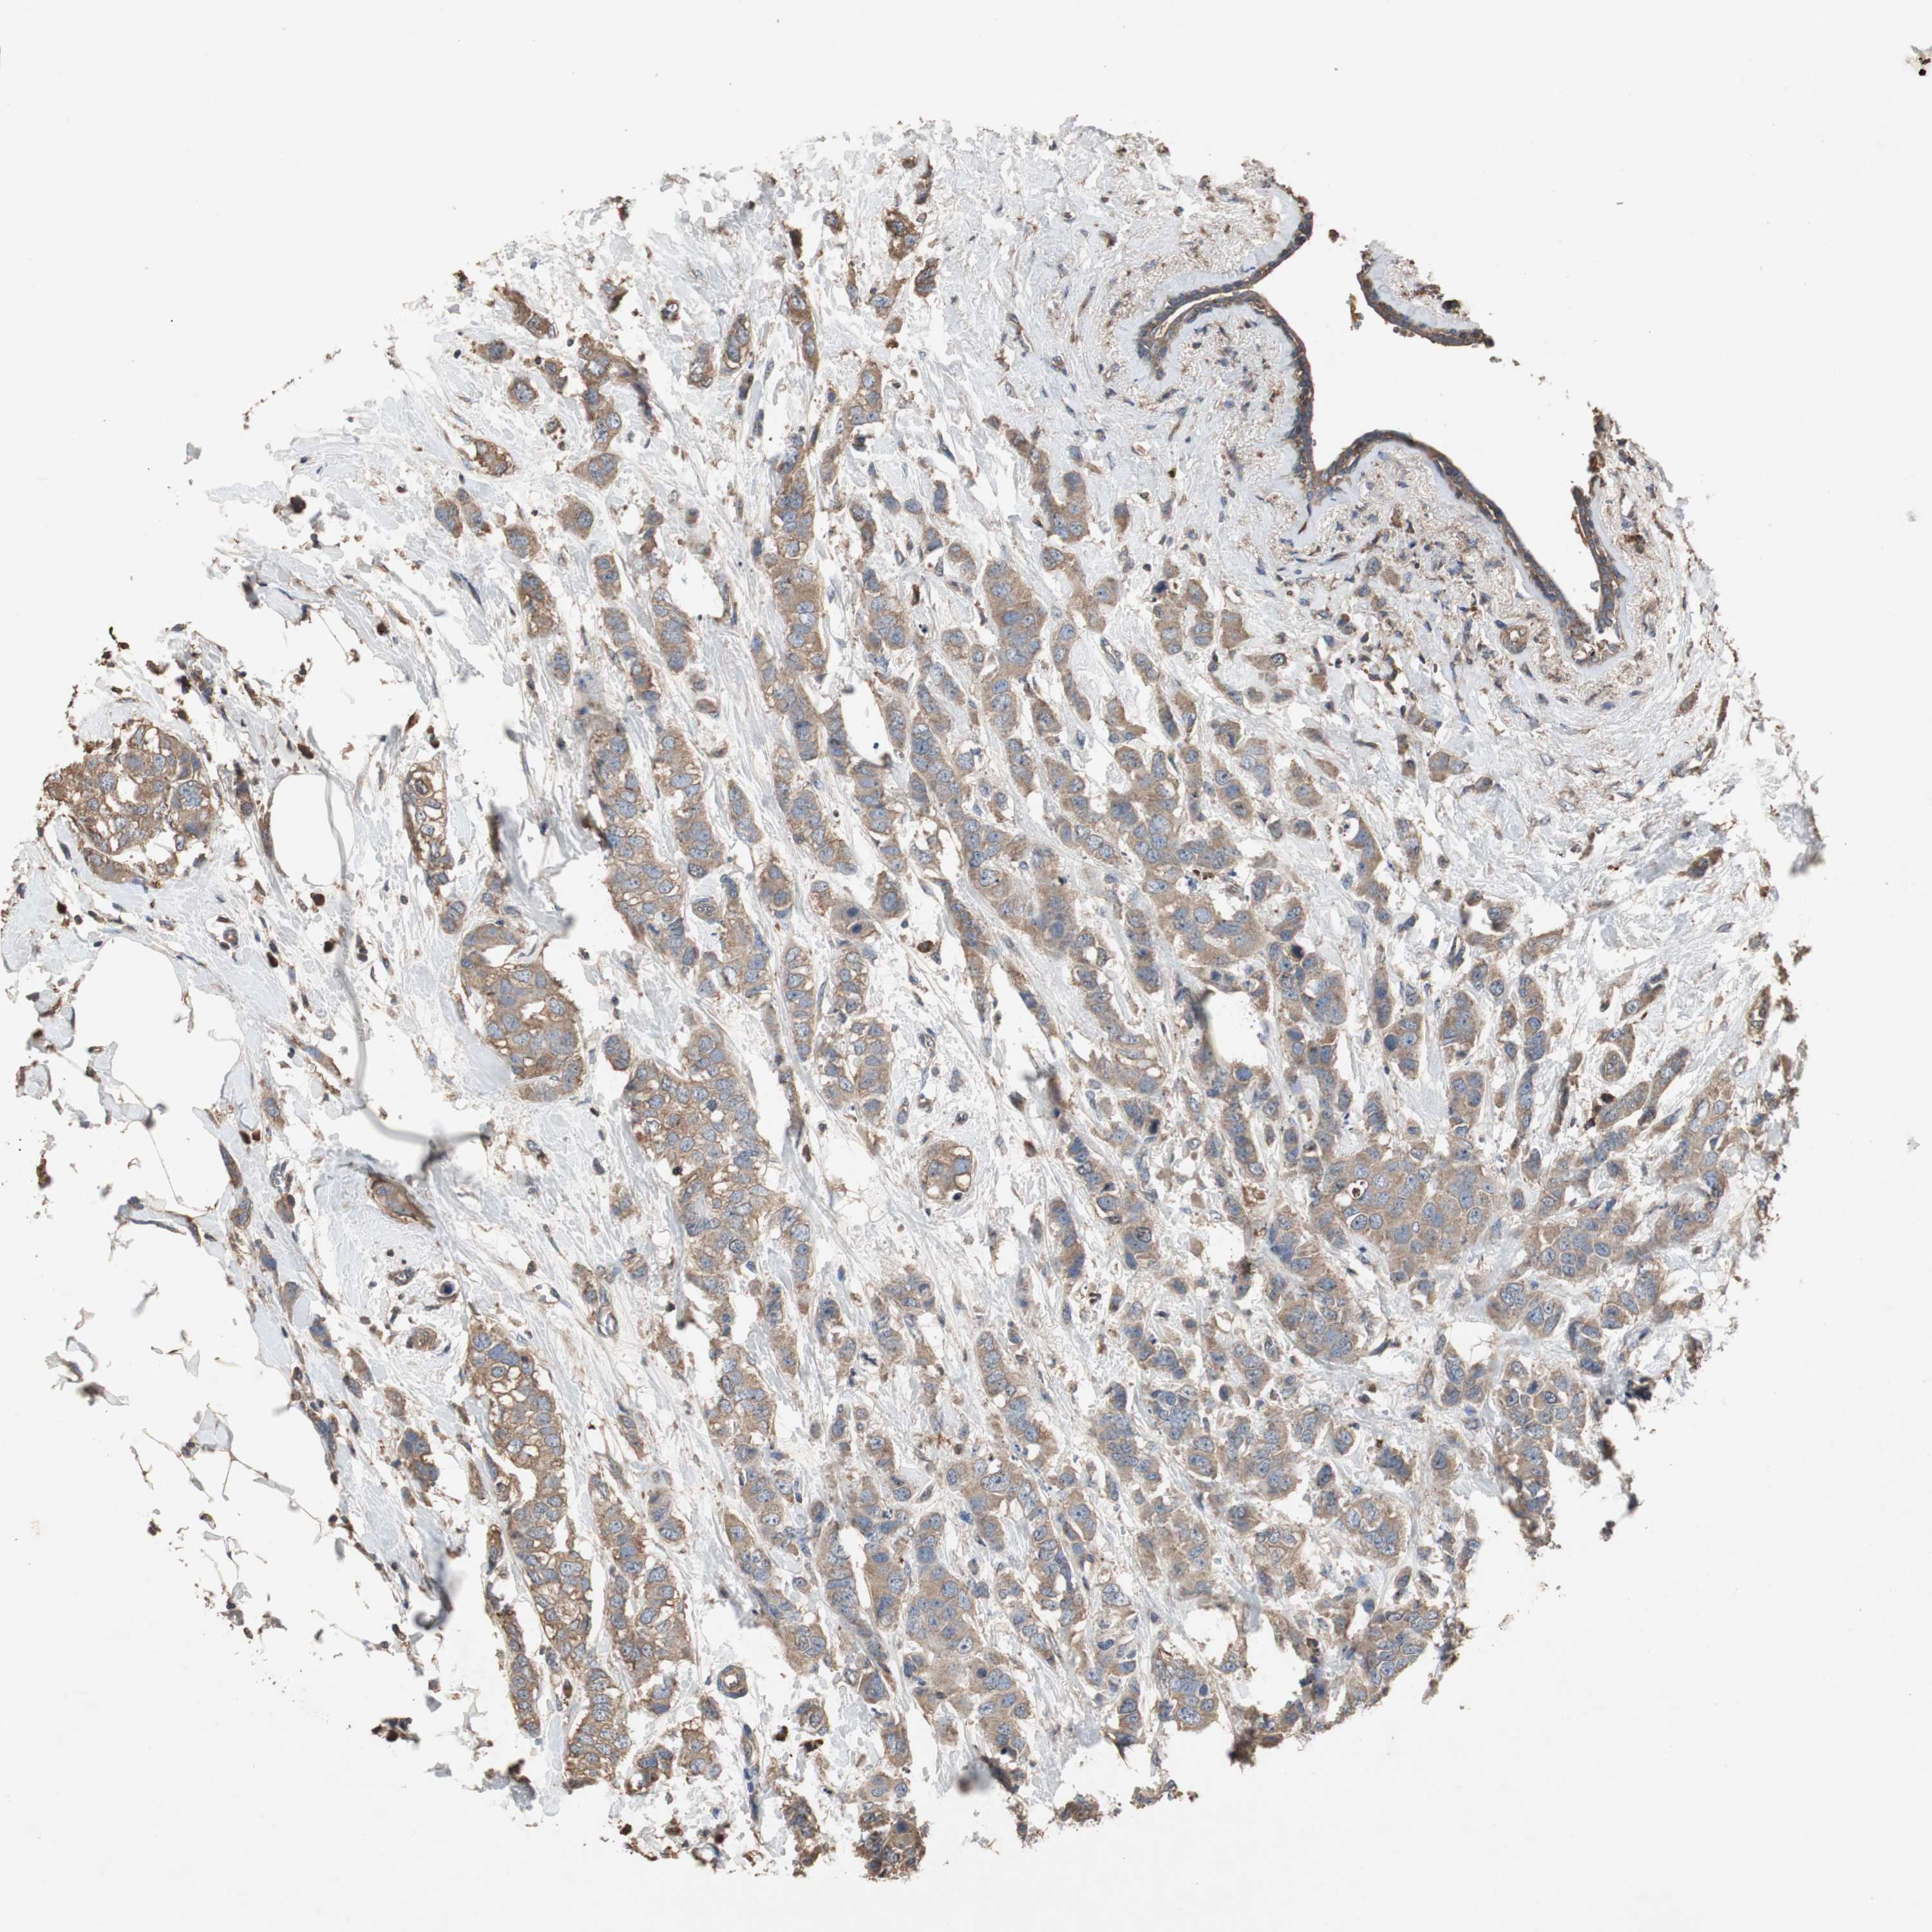

CANCER BREAST CANCER Show tissue menu

BRCA TCGA BRCA VALIDATION PROTEIN EXPRESSION